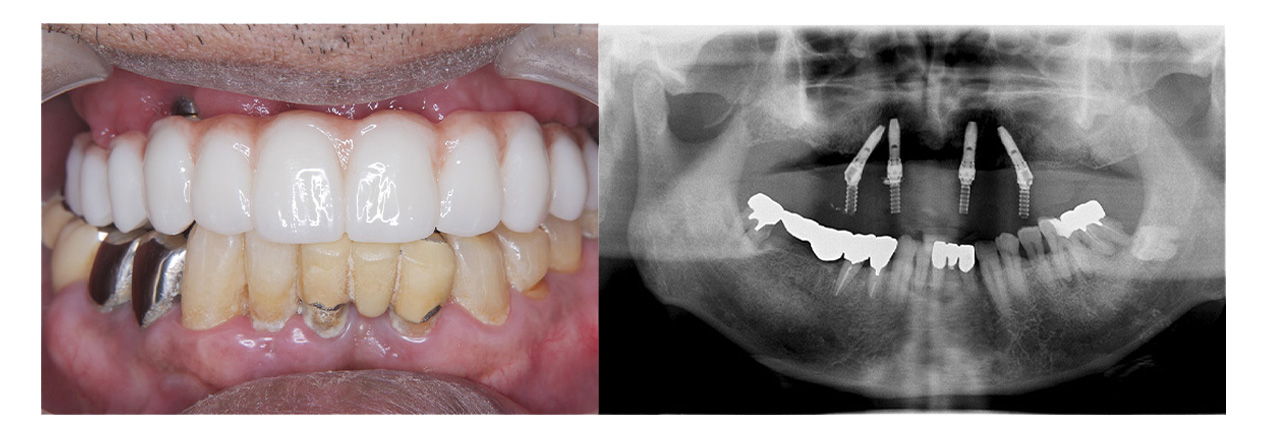

症例その1オールオン4

• Before

• After

咀嚼、審美障害。歯周病でグラグラな歯を全部抜歯してオールオン4で治療した症例。